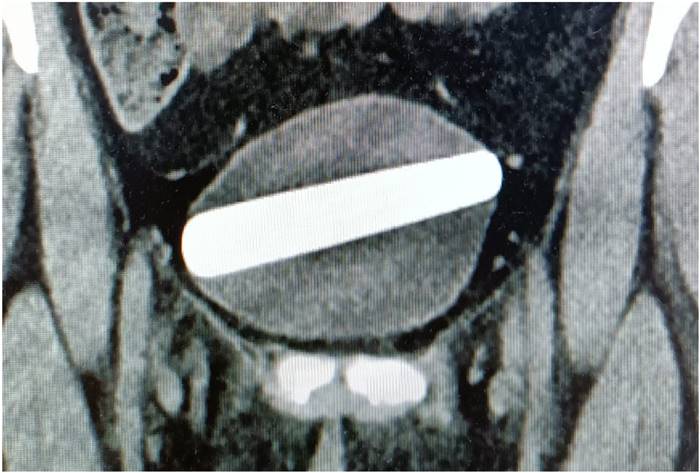

โดยคนไข้ยอมรับว่า ได้สอดดิลโด้ซึ่งมีลักษณะเป็นแท่งคริสตัล ยาวเกือบ 10 เซนติเมตร กว้าง 2.5 เซนติเมตร เข้าไปในร่างกายระหว่างทำกิจกรรมทางเพศ แต่มันพลาดหลุดเข้าไปในกระเพาะปัสสาวะ เธอใช้เวลาราว 2-3 ชั่วโมงพยายามดึงวัตถุดังกล่าวออกมาเอง แต่ก็ไม่สำเร็จ สุดท้ายจึงตัดสินใจมาขอความช่วยเหลือจากแพทย์

แพทย์ฉุกเฉินทำการอัลตราซาวด์ จนพบว่าวัถตุแปลกปลอมอยู่ภายในกระเพาะปัสสาวะของหญิงรายนี้ โดยทอดตัวแนวขวาง หลังจากนั้นจึงมีการให้ยาปฏิชีวนะผ่านทางสายน้ำเกลือ จึงได้ให้ยาสลบแล้วทำการดึงดิลโด้ดังกล่าวออกมาด้วยวิธีการส่องกล้องทางเดินปัสสาวะ ทั้งนี้ คนไข้สามารถกลับบ้านได้ในวันนั้น หลังสามารถถ่ายปัสสาวะได้ตามปกติแล้ว

ภาพจาก Yehuda Noyman